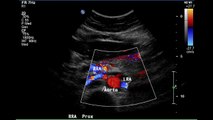

Renal Artery Stenosis

by DR TAHIR A SIDDIQUI ( consultant sonologist ) Gujranwala. Pakistan.